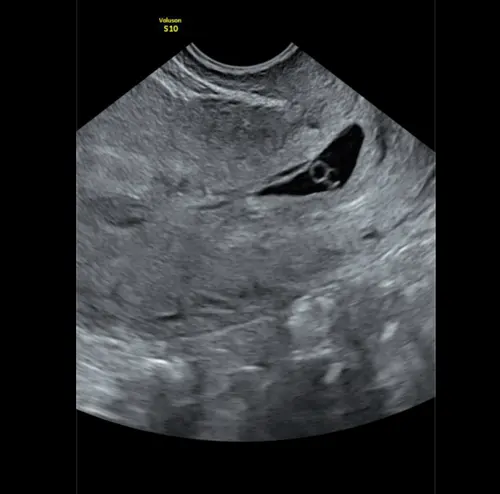

Zaterdag volgde de echo. Daar was het dan: 5,5 weken, maar nog geen hartslag. Op de echo was al te zien dat de miskraam al bezig was.